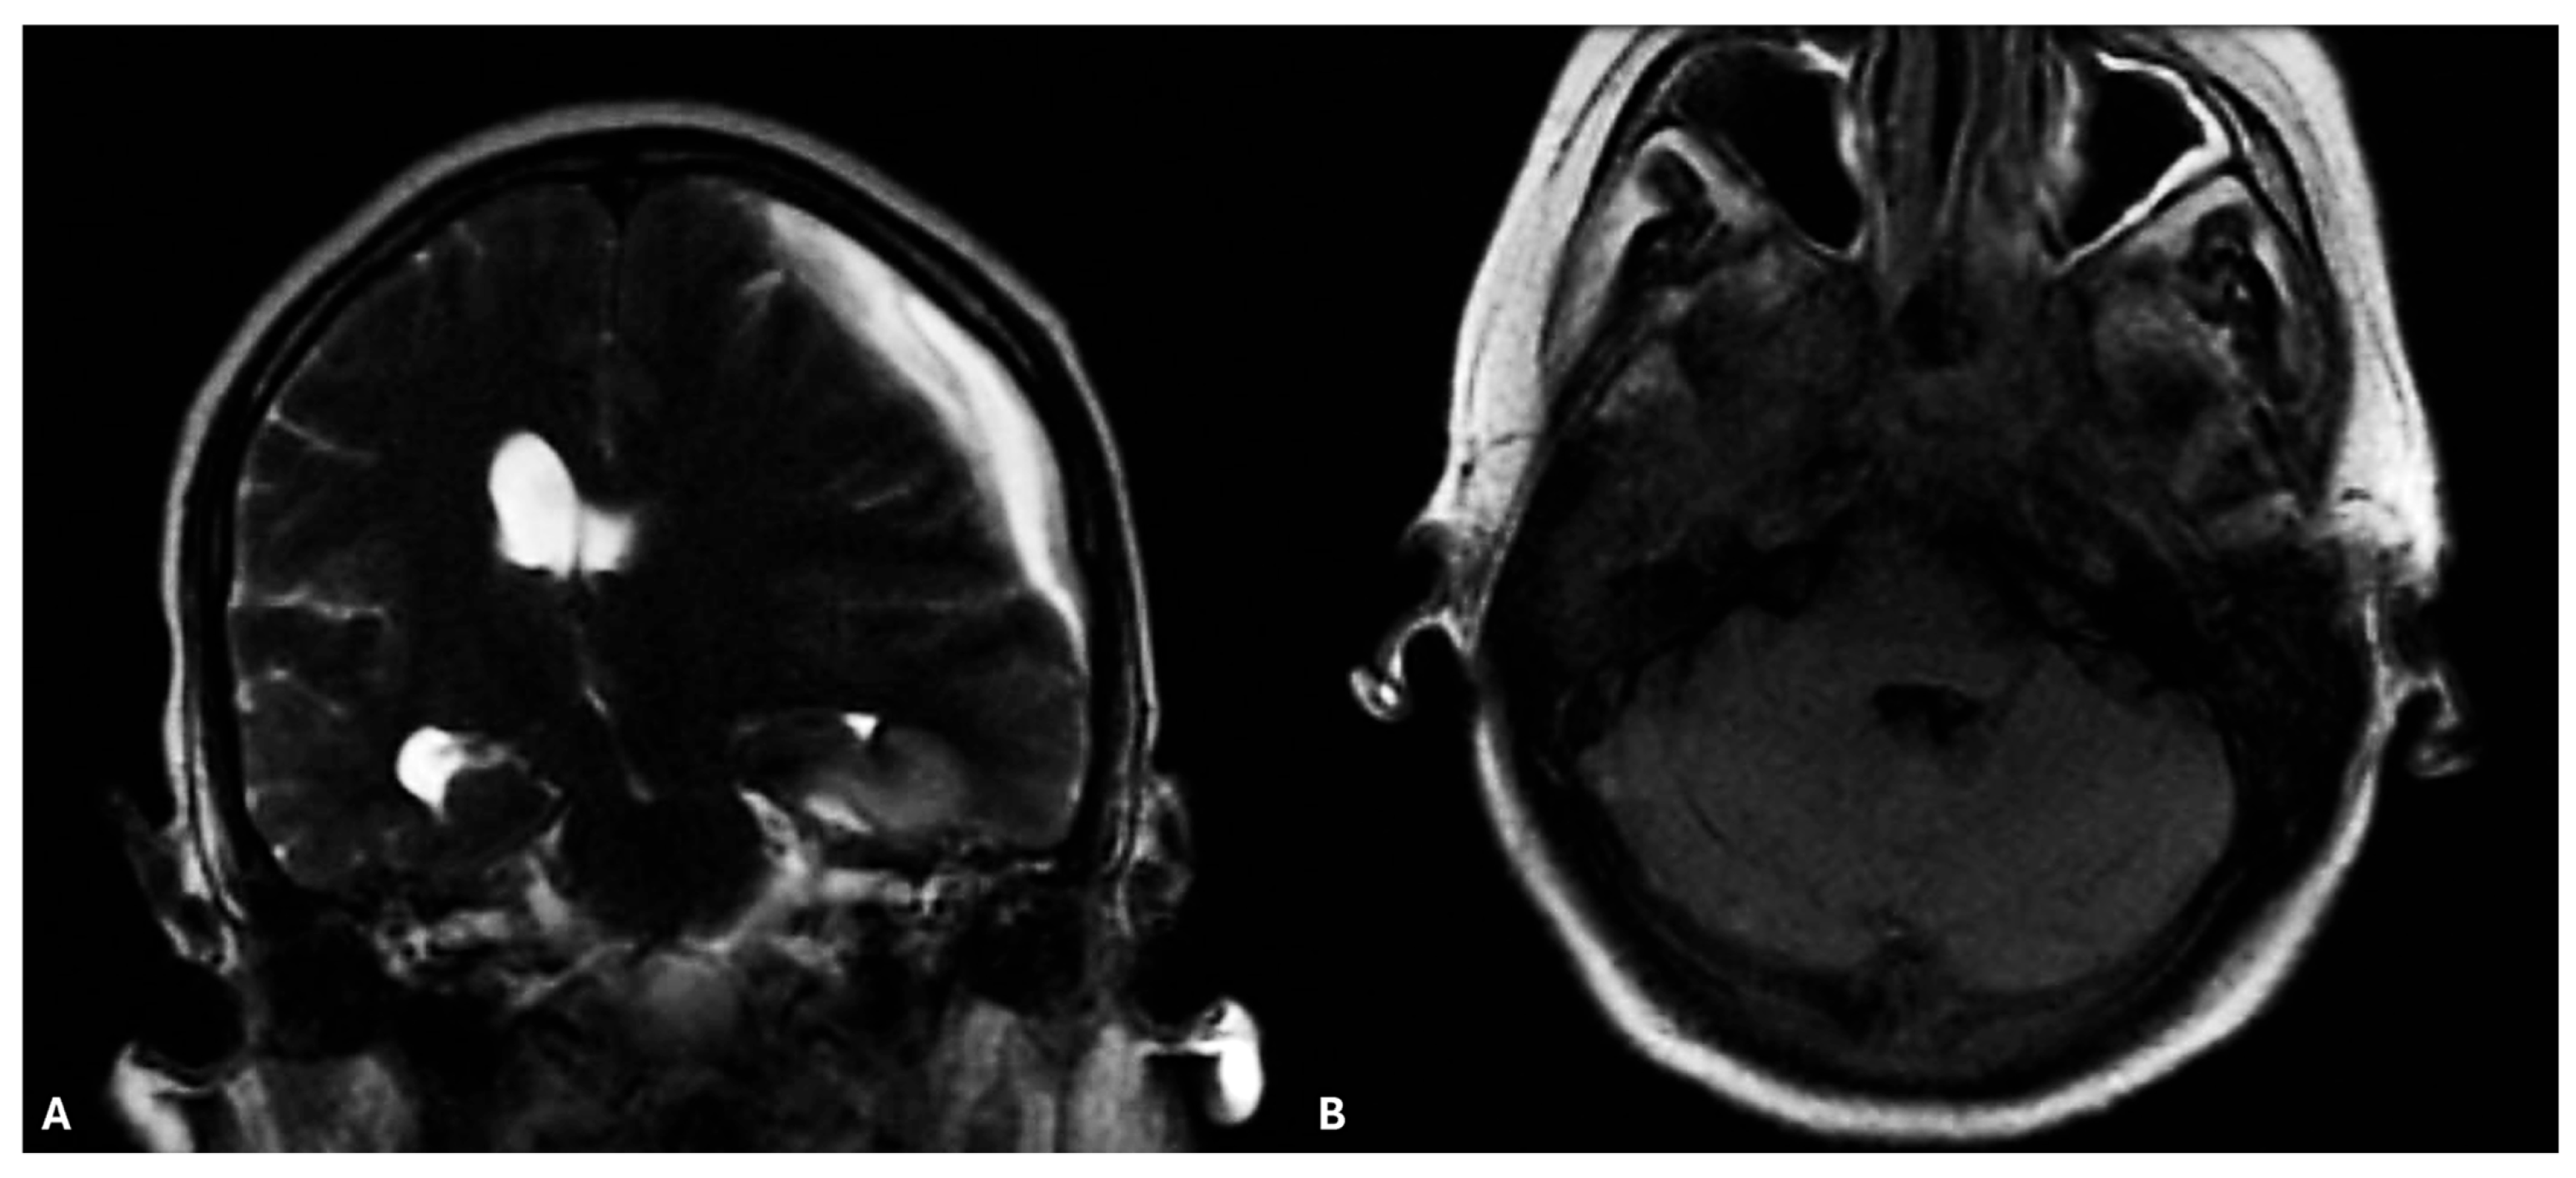

2. Case Report